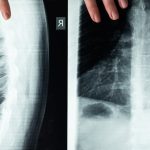

Comprendre les hernies discales

Les hernies discales se produisent lorsque le matériau gélatineux à l’intérieur d’un disque intervertébral se déplace à l’extérieur de sa position normale, entraînant la compression des nerfs environnants. Cela peut provoquer des douleurs intenses, des engourdissements, et même des faiblesses musculaires. Les personnes souffrant de hernies discales chroniques font souvent face à des inflammations sévères qui peuvent gravement affecter leur qualité de vie.

La décompression neurovertébrale se concentre sur la réduction de cette pression tout en permettant la régénération des structures nerveuses. Cette approche crée un espace autour de la moelle épinière et des nerfs, limitant ainsi l’inflammation. En augmentant le volume du canal rachidien, la décompression aide à soulager la douleur et à favoriser la guérison. Plusieurs techniques peuvent être appliquées, variant de la décompression non chirurgicale à des interventions plus invasives.

Techniques de décompression

Il existe divers traitements pour mettre en œuvre la décompression neurovertébrale. Les techniques non chirurgicales incluent des méthodes comme la traction vertébrale, qui mobilise les disques intervertébraux afin de réduire la pression exercée sur les nerfs. En parallèle, les procédures chirurgicales peuvent impliquer l’ablation de petits fragments osseux ou des tissus envahissants qui contribuent à l’inflammation.